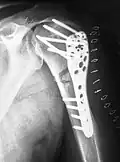

- Die winkelstabile Platte am proximalen Humerusschaft

-

Eine Fraktur am oberen Ende des Humerus -

Versorgung mit winkelstabiler Platte -

Ansicht in anderer Ebene